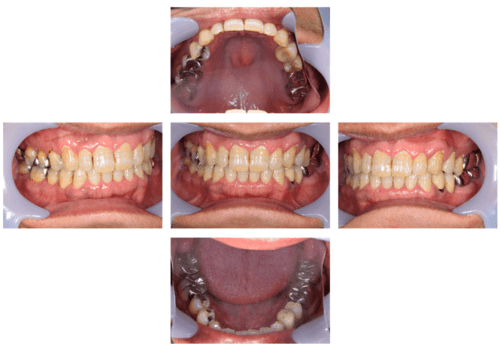

インプラント治療の症例4

レントゲン写真

- Befor

- After

口腔内写真

| 年齢 | 50代・男性 |

|---|---|

| 主訴 | 部位:左下6番7番 主訴:左下奥歯腫れて痛い。 |

| 治療内容 | 左下6番抜歯、左下6番7番骨造成、インプラント埋入 |

| 治療費 | 合計:1,232,000円 ・内訳 診断料:55,000円 サージカルガイド2本:66,000円 GBR:110,000円×2本 埋入料:165,000円×2本 静脈内鎮静麻酔:77,000円 2次OPE:22,000円×2本 仮歯:55,000円×2本 上部構造(フルジルコニア):165,000円×2本 (2023年1月現在) |

| 治療期間 | 約8ヶ月 |

| リスク・副作用 | リスク・副作用 |

| 治療方針 | 元々支台歯に負荷がかかりやすいとされている延長ブリッジを抜歯し、1本単体でしっかりかめるようにインプラントを2本埋入した。骨吸収も進んでいたため、※GBR法で骨造成を同時に行った。 治療と並行して、全顎的な歯周病治療も行い、今後は歯周病が進行しないよう、こまめにメンテナンスに通っていただく。 |

| 特記事項 | ※1 GBR・・・骨再生誘導法。骨の高さや厚みを人工骨や人工膜などを使用し再生する方法 |

| 担当者所見 | 6番は歯根分割された被せ物が7番の欠損部との延長ブリッジとされており、強い咬合と歯周病も相まって負荷がかかり動揺し、歯として機能しなくなったため、抜歯となった。 |